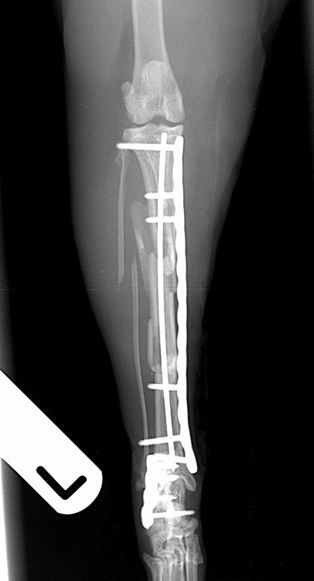

Fig. 1 A 6-year-old DSH cat with comminuted fractures of the tibia, fibula and calcaneus

Fig. 2 Immediate post-operative radiographs. A 2.4mm PAX plate with an intra-medullary pin has been used to repair the tibial fracture. A 2.0mm PAX plate has been used to repair the comminuted calcaneal fracture